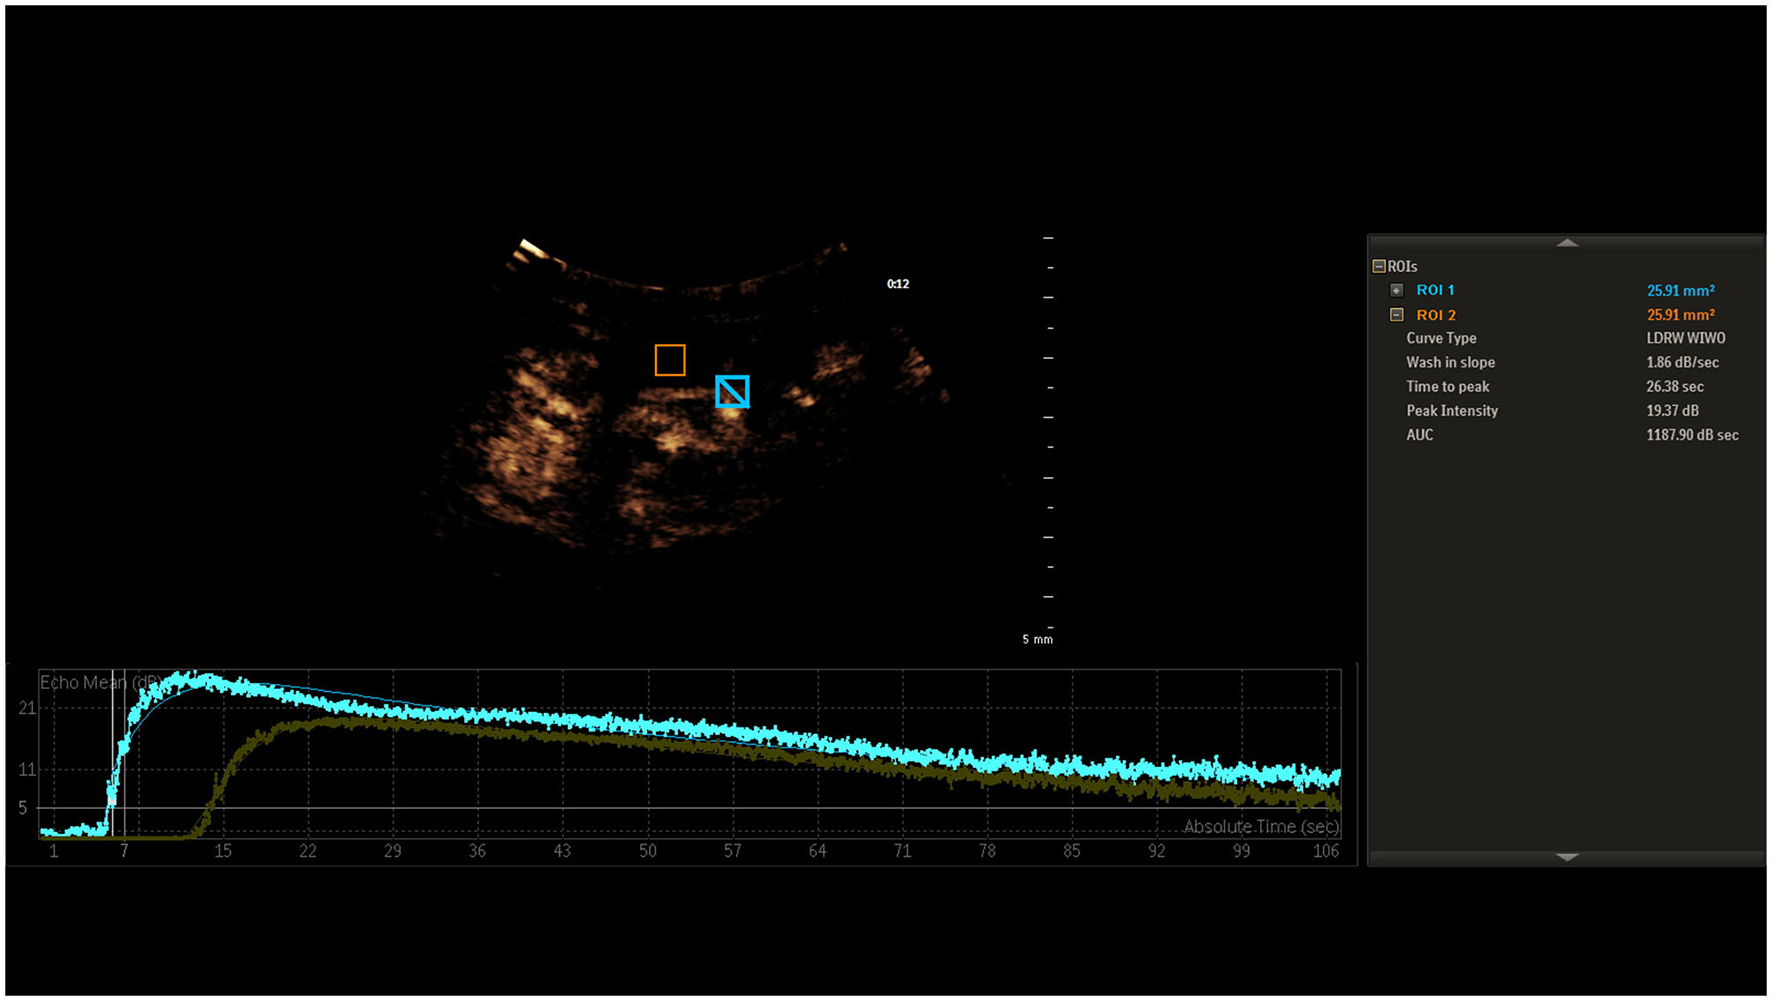

Analysis of the imaging data was executed through uninterrupted video capture, with time-intensity curves being isolated post-recording by a seasoned ultrasonographer. The in-built software automatically processed these curves after targeting the ICA and IJV, as illustrated in Figure 1. Initial mean intensity for arterial and venous segments was extracted from an early spectrum segment lacking signal boost. A persistent mean intensity elevation of 5 dB or greater over the baseline was earmarked as the onset of signal amplification for both ICA and IJV, based on the methodology suggested by Cavaillon and Chrétien (19). The time difference between these onset points in the ICA and IJV was denoted as CCT.

Figure 1

Time-intensity curves for ICA and IJV, highlighting the onset of signal amplification at a 5 dB mean intensity elevation. The interval between these onset points is labeled as CCT.